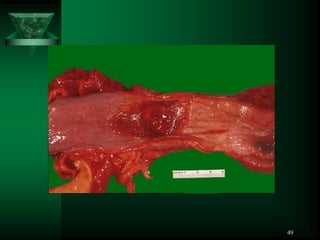

АДЕНОКАРЦИНОМ НА СТОМАХА

50